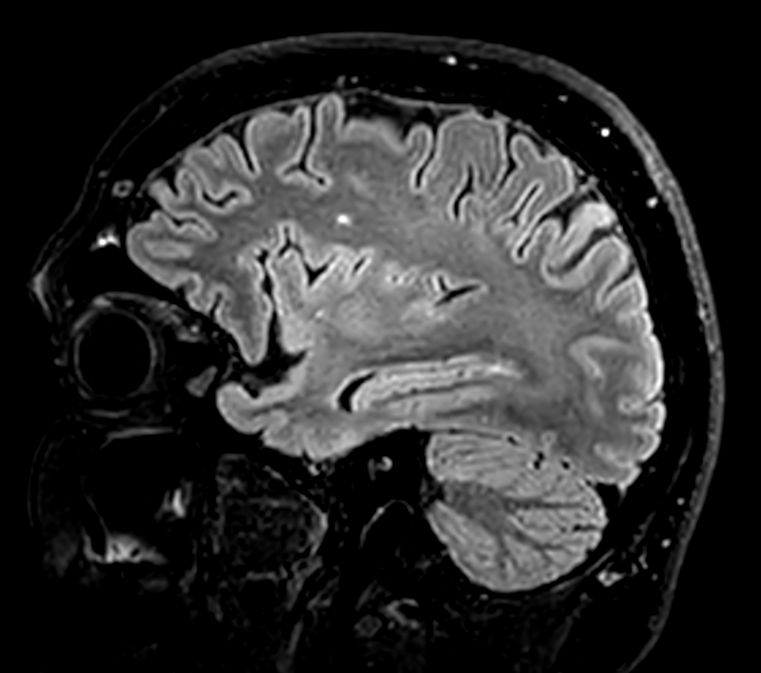

Sagittal 3D VIEW - T1w TSE

3D VIEW - T1w TSE (coronal reformat)

3D VIEW - T1w TSE (axial reformat)